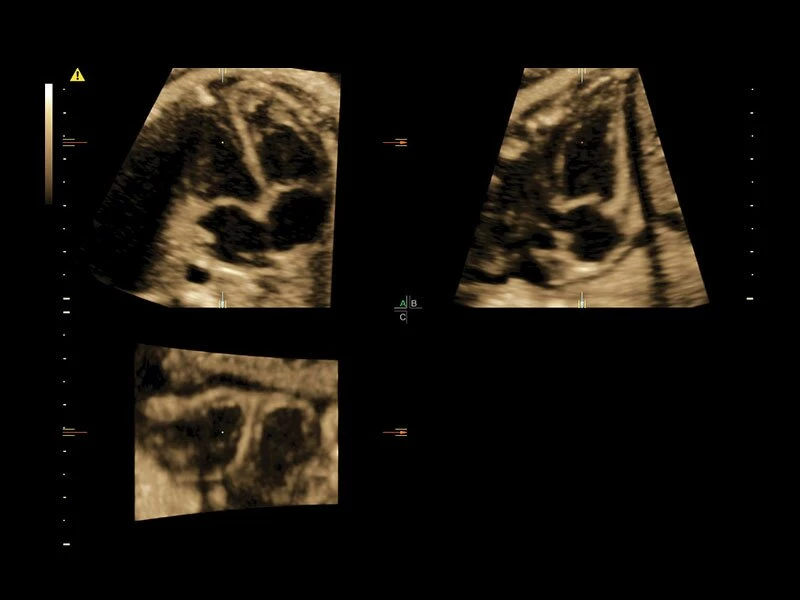

Объемное сканирование Voluson — 3D/4D вашей мечты

Объемное УЗИ на Voluson E10 — это не просто потрясающе красивая картинка, это ценный инструмент получения дополнительной информации при обследовании женщин.

Voluson E10 поддерживает инновационные технологии формирования изображений — HDlive Silhouette и HDlive Flow, которые позволяют увидеть мельчайшие детали. Алгоритм SonoRenderlive упрощает рабочий процесс и дает возможность реконструировать изображение поверхностей, определяя область перехода между тканью и жидкостью.

Инновационная технология визуализации HDlive обеспечивает получение реалистических изображений за счет эффекта объемного зрения, повышая достоверность клинической оценки. Теперь режим HDlive дополняют две новые функции:

- Технология HDlive Silhouette — задает разный уровень прозрачности, помогая выявлять контуры внутренних структур и точнее оценивать состояние плода в первом триместре.

- Режим 3D SonoRenderLive – инновационная система, позволяющая определять четкие границы лица и конечностей плода в объеме, избавляясь при этом от лишних артефактов, шума и помех.